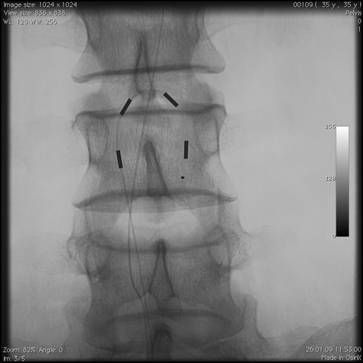

После тщательной обработки операционного поля выполняется небольшой разрез в проекции остистых отростков, на фоне тщательного гемостаза отсепаровыватся паравертебрально поясничная фасция на уровне пункции эпидурального пространства (зависит от уровня неврологического проявления боли). Под углом 45• сагиттально и по направлению к средней линии под местной анестезией иглой Туохи выполняется пункция эпидурального пространства под контролем ЭОП. Также, для контроля попадания в эпидуральное пространство используется шприц низкого давления. При нахожении кончика иглы в эпидуральном пространстве исчезает ощущение резистентости в шприце, жидкость (как правило стерильная вода для иньекций) свободно проходит. Затем по игле вводится проводник для дополнительного контроля свободного проведения электрода. Далее под контролем ЭОП на нужный уровень проводятся электроды. Вид и размер элекродов подбирается в зависимости от задач, решаемых хирургом. Электрод проводится на микропроводниках, входящих в набор и облегчающих установку. Форсированное проведение электрода не рекомендуется. После установки электрода наружная контактная группа присоединяестся кабелем к программатору врача или тестовому стимулятору для подтверждения результатов тестовой стимуляции. При получении положительного результата приступают к монтажу всей системы.

Электроды располагают параллельно ближе к средней линии. При установке одноканальной системы гомолатерально ближе к средней линии. Чем латеральнее друг от друга находятся электроды, тем шире поле воздействия сигнала генератора.

На представленных ниже рисунках отображены основные этапы установки системы.

Установка постоянных электродов

Рентгенконтроль при проведении электродов

Флюороскопический контроль во время операции является необходимым условием для контроля положения иглы, уровня и места установки дистального конца электрода. Электроды чаще всего устанавливаются ростральнее неврологического уровня боли на стороне симптоматики.